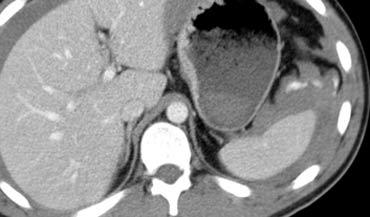

Bên trái là hai ví dụ khác về đường rách gan.

Các đường rách có thể có hình sao, như ví dụ bên trái, hoặc hình phân nhánh như ví dụ bên phải.